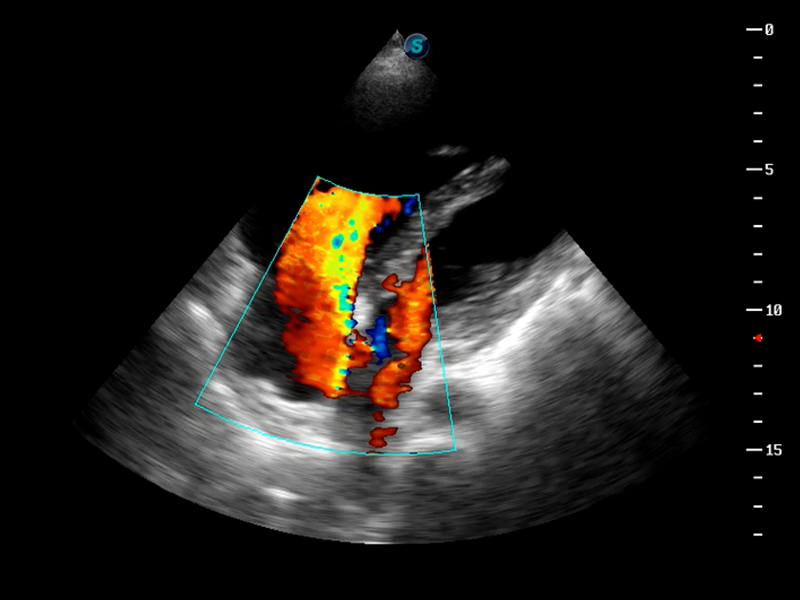

S9便携式彩色多普勒超声诊断仪是16877太阳集团研发的高端便携彩超设备,外观设计新颖、产品性能卓越。S9在便携超声领域采用了突破传统的触摸屏交互设计,并以先进的软件硬件技术和设计理念,为您带来清晰的图像质量、稳定的工作性能和便捷的操作体验。

TDI组织多普勒成像

AutoC智能血流追踪